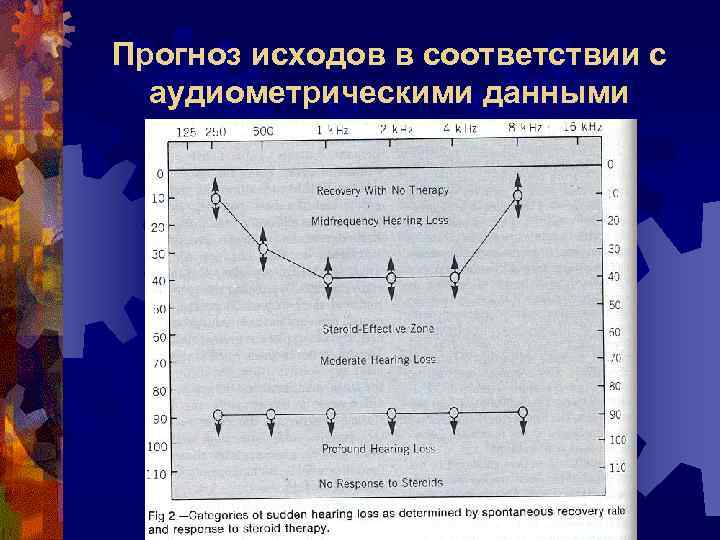

Прогноз исходов в соответствии с аудиометрическими данными